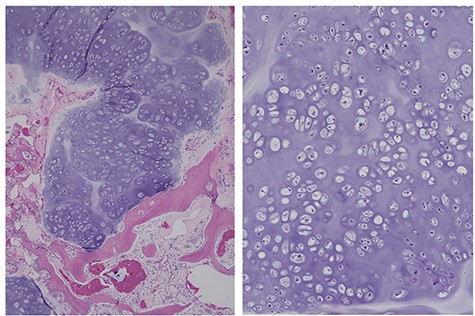

A needle biopsy of the new tissue revealed no atypical cartilaginous tissue. However, taking into consideration the clinical course, chondrosarcoma was diagnosed. Surgery was performed with almost the same incision, but the incision was extended to the distal sacrum (Fig. 1C). The multifidus muscle was removed from the distal sacrum in the same way as in the primary operation (Fig. 1C). The tumor compressed the L5 nerve root and was resected in several blocks. The pathological diagnosis of the resected material was a chondrosarcoma arising from the osteochondroma (Fig. 2). The pain was relieved postoperatively.

The same case as in Fig. 1, diagnosed as a chondrosarcoma. The resected recurrent tumor has a nodular structure with cartilaginous matrix. A permeative pattern is observed (left). The magnified view shows dense chondrocytes (right).